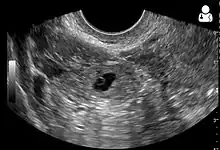

Transvaginal ultrasonography

An ultrasound showing a gestational sac with fetal heart in the fallopian tube has a very high specificity of ectopic pregnancy. It involves a long, thin transducer, covered with the conducting gel and a plastic/latex sheath and inserted into the vagina.[32] Transvaginal ultrasonography has a sensitivity of at least 90% for ectopic pregnancy.[5] The diagnostic ultrasonographic finding in ectopic pregnancy is an adnexal mass that moves separately from the ovary. In around 60% of cases, it is an inhomogeneous or a noncystic adnexal mass sometimes known as the "blob sign". It is generally spherical, but a more tubular appearance may be seen in case of hematosalpinx. This sign has been estimated to have a sensitivity of 84% and specificity of 99% in diagnosing ectopic pregnancy.[5] In the study estimating these values, the blob sign had a positive predictive value of 96% and a negative predictive value of 95%.[5] The visualization of an empty extrauterine gestational sac is sometimes known as the "bagel sign", and is present in around 20% of cases.[5] In another 20% of cases, there is visualization of a gestational sac containing a yolk sac or an embryo.[5] Ectopic pregnancies where there is visualization of cardiac activity are sometimes termed "viable ectopic".[5]

A pregnancy not in the uterus[33]